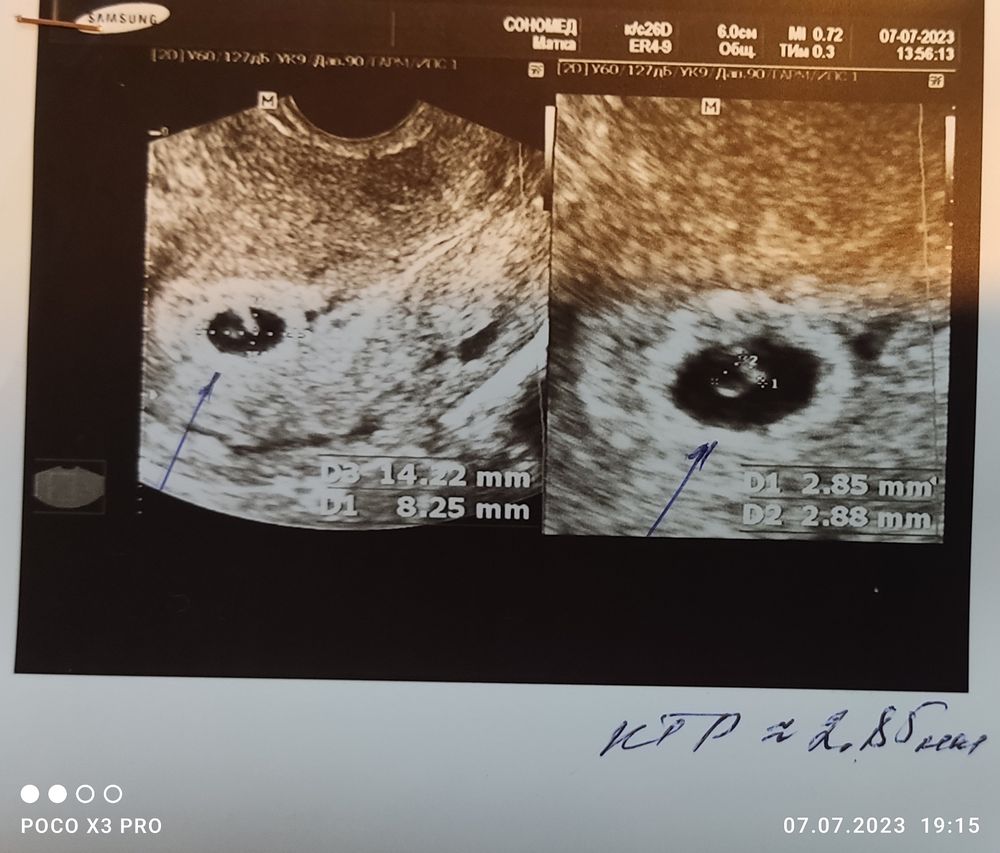

Поздравляю вас)) У меня по мес срок 5+6 недель,по УЗИ вчера поставили срок 5+1 неделя,пя 11 мм,Ктр 2,8 мм и чсс 112 уд мин

Алена, я тоже пойду, что бы бы спокойной) мне вот такой снимок дали Изображение